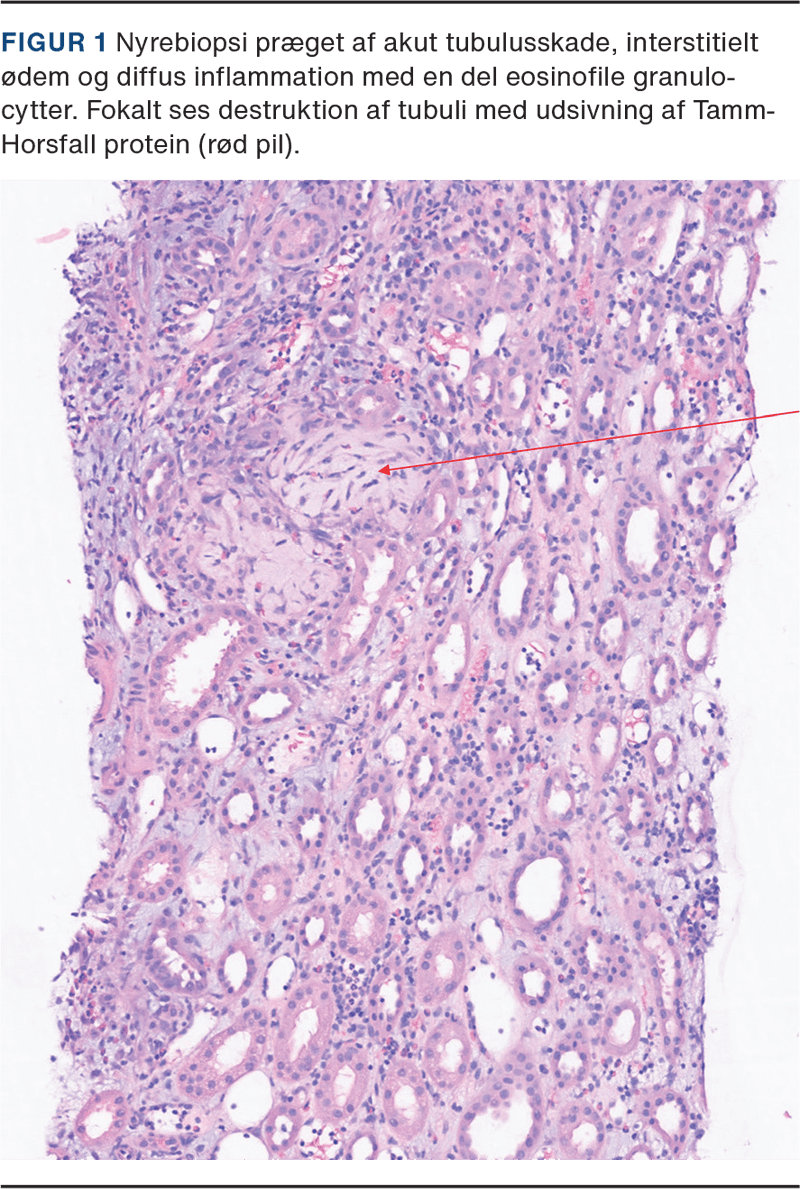

På tredje indlæggelsesdøgn steg P-kreatinin til 440 μmol/l, eGFR 16 ml/min/1,73m2, fosfat til 1,87 mmol/l (0,72-1,49 mmol/l), p-kalium til 4,1 mmol/l, og HCO3 var uændret. Patienten havde vedvarende diureser: 0,8 ml/kg/t, vægten var 86,6 kg, og patienten havde nu fulminant nonoligurisk nyresvigt. Patienten blev overflyttet til højtspecialiseret afdeling grundet rapidt progredierende nyresvigt med henblik på stillingtagen til biopsi, behandling og muligt behov for dialyse. Der blev opstartet behandling med prednisolon tablet 80 mg × 1 dagligt, og to døgn efter blev der foretaget nyrebiopsi. Denne viste medikamentel betinget interstitiel nefritis med let akut tubulær skade, interstitielt ødem og inflammation med en del eosinofile granulocytter. Stedvis sås destruktion af tubuli, der morfologisk lignede billedet ved en akut tubulointerstitiel nefritis (ATIN) (se Figur 1).